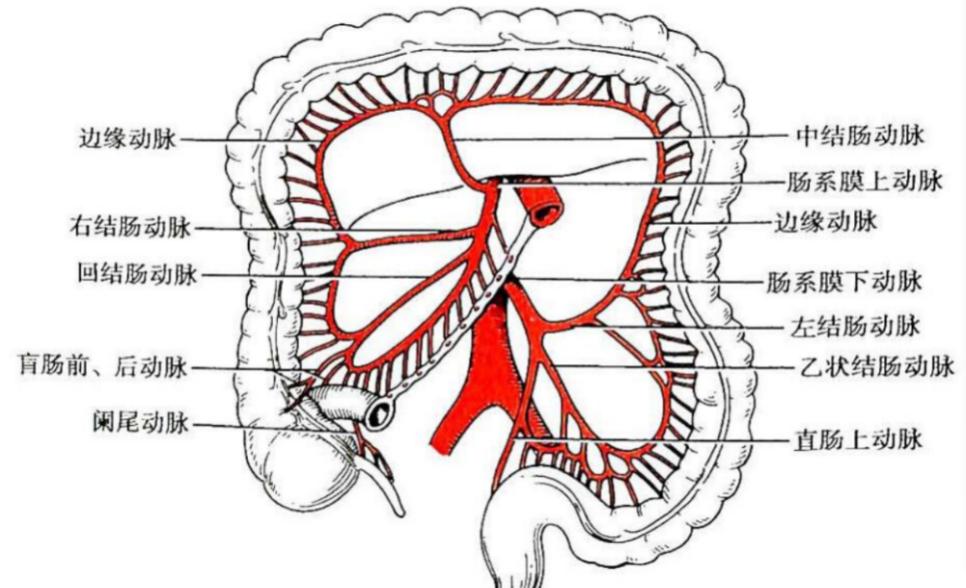

肠系膜上动脉是腹主动脉发出的重要分支,供应了供应所有小肠、右半结肠和大部分横结肠,若该血管被栓子完全堵塞,将导致所供应的肠管出现急性缺血坏死,甚至出现低血容量休克或感染性休克等。

该病栓子多为心源性,多来自风湿性心脏病、冠心病、房颤等;也有部分为血管源性,如动脉硬化斑块脱落、动脉瘤附壁血栓脱落等;部分患者有血管介入检查或治疗操作史。本病早期多表现为“Bergan三联征”(剧烈而无相应体征的腹痛、器质性心脏病和并发房颤的心脏病、胃肠排空障碍表现例如腹泻、血便),病史采集尤为重要。本病病程早期外周血白细胞可明显升高,腹部X线片可见气液平面、肠腔积气、肠管扩张等肠梗阻征象。动脉造影为最直观准确的诊断方法,可以明确肠系膜上动脉全部情况。CTA对该病诊断的特异性和敏感性可高达100%和73%。 应对该病, 应尽早诊断,尽早手术治疗,迅速去除血管内的栓子,恢复肠系膜上动脉的血液灌注。对于早期高度怀疑者,若条件允许可行动脉造影,根据造影选择是否介入治疗。若出现肠坏死时,则尽早手术切除坏死肠管,避免出现感染性休克。